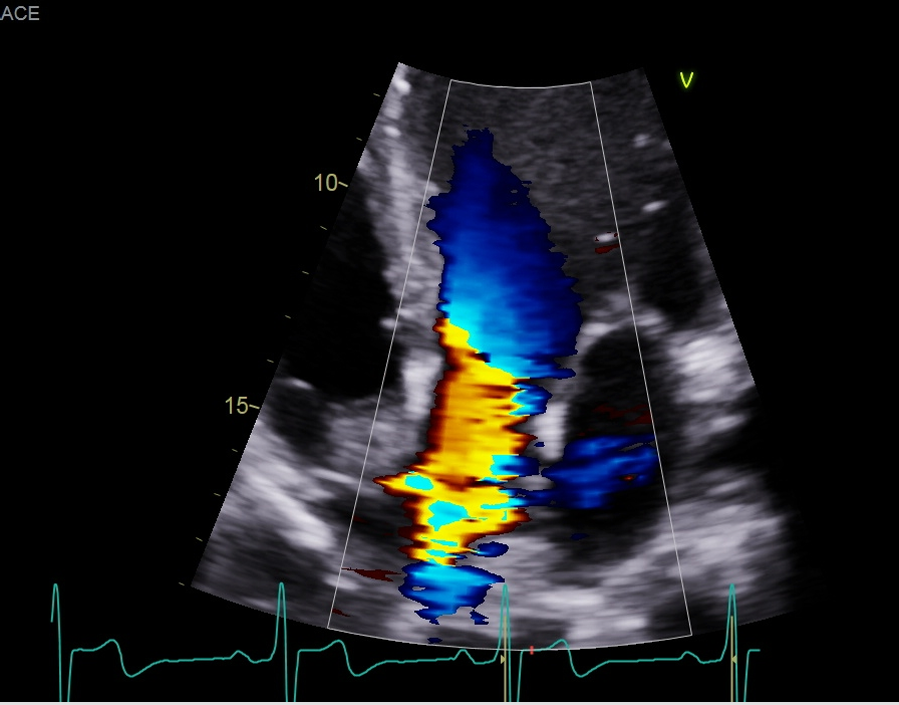

when we do our color flow what are we looing for the step we look at the pulmonary vein with color?

So, we look at the color of the pulmonary veins and for any MR, the normal flow pulmonary vein to LA to MV and the to LV, so any blue flow is going to be that MR reaching back and this red flow will be the pulmonary vein